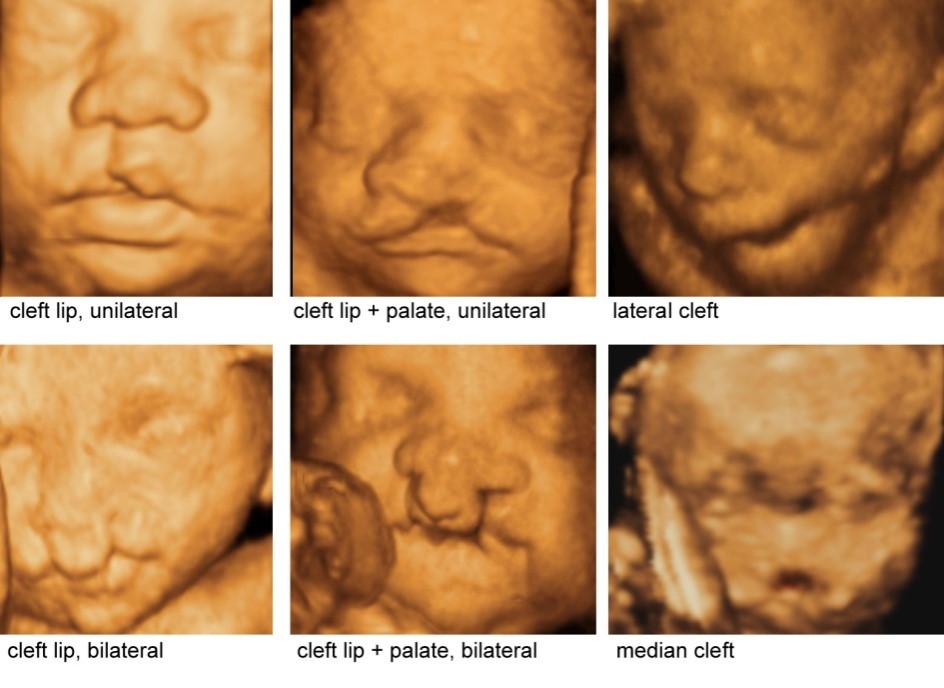

"Как правило, о пороке узнают на на 20-21 неделе. Родители, уже зная, что у них родится ребенок с патологией, заблаговременно направляются в наш центр для родоразрешения, после чего наши специалисты: неонатальные врачи, челюстно-лицевые хирурги оказывают медицинскую помощь новорожденному. То есть новорожденные с расщелиной губы выписываются уже прооперированными и практически здоровыми. Преимуществом является то, что нет необходимости ждать длительное время, а это значит и родители, и их близкие психологически переносят все легче", – рассказывает казахстанский врач.